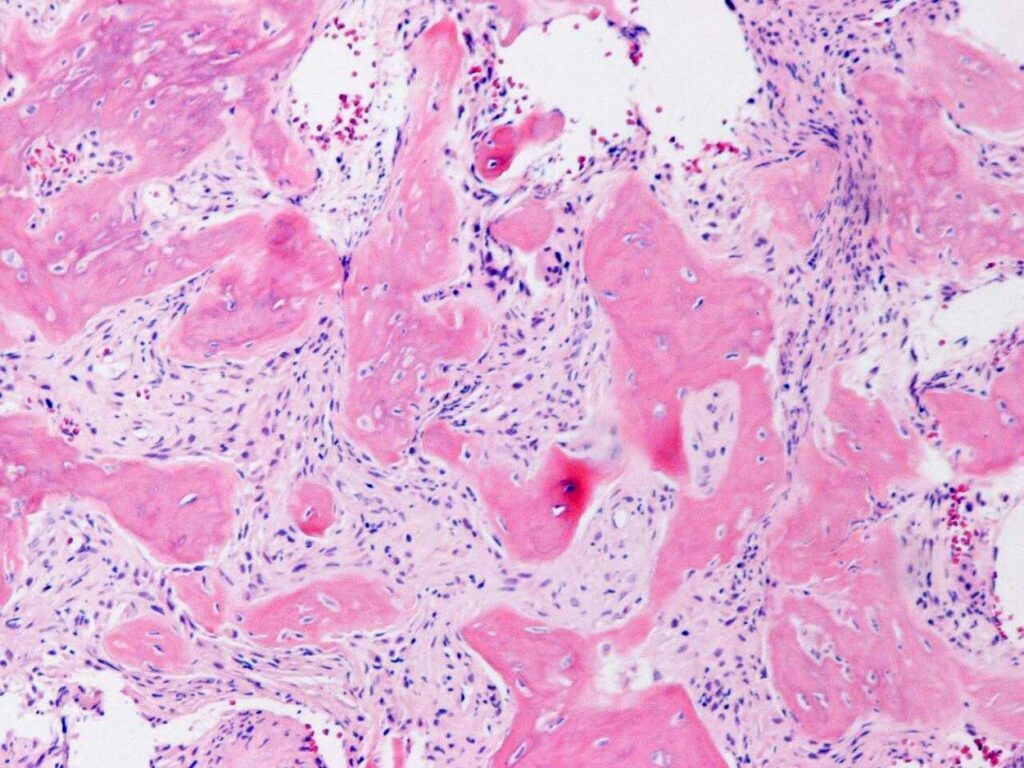

PATHOLOGY

Low Grade Intraosseous Osteosarcoma is a low-grade malignancy, similar to parosteal osteosarcoma.

Microscopic

• Display bundles of spindle cell proliferations with variable osteoid production, low cellularity, low mitotic rate, and minimal pleomorphism (Fig. 9 & 10).

• The presence of infiltrative margins and the absence of marked cellular atypia helps to differentiate low grade intraosseous osteosarcoma from benign entities.

Fig. 9

Fig. 10

Fig. 9 & 10: Microscopic Pathology. Low and high power views with irregular woven bone trabeculae in a moderately cellular fibrous tissue. Atypical cells displaying hyperchromatic nuclei are closely associated with the irregular woven bone trabeculae.